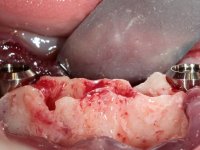

Two dental implants were planned in the CBCT scan, in the area of the inferior canines. The dental extractions were performed and, simultaneously, the alveolar crest was flattened and the implants were placed. Three issues were considered while implant placement: parallelism of the axis, same height of the implant’s neck, and same position in the coronal plan. This 3D insertion is essential to have a good retention of the overdenture in the future. Patient’s removable denture was fixed in the dental lab, to include the extracted teeth, and a soft-tissue relining was done over the healing abutments. After the osseo-integration period, a first impression was done with an open-tray and a doble-mix technique. This dental impression allowed the production of screwed wax-rims and an individual tray for a functional impression. A second impression, final, was done with an individual tray with a monophasic silicone. The occlusal wax-rims were correct in the mouth according to the full denture guidelines. Special care was taken with the occlusal vertical dimension and the support in the soft-tissues. A silicone bite registration material was used to better defined the intermaxillary relations. Teeth set-up was done in the dental lab with the selected tooth color. Due to the fact that the base was screwed to the dental implants, the teeth set-up was functionally evaluated in the mouth. Another silicone bite registration material was used to allow final occlusal adjustments. Finally, the locators were screwed and the retention nylons were selected according to the patient needs.